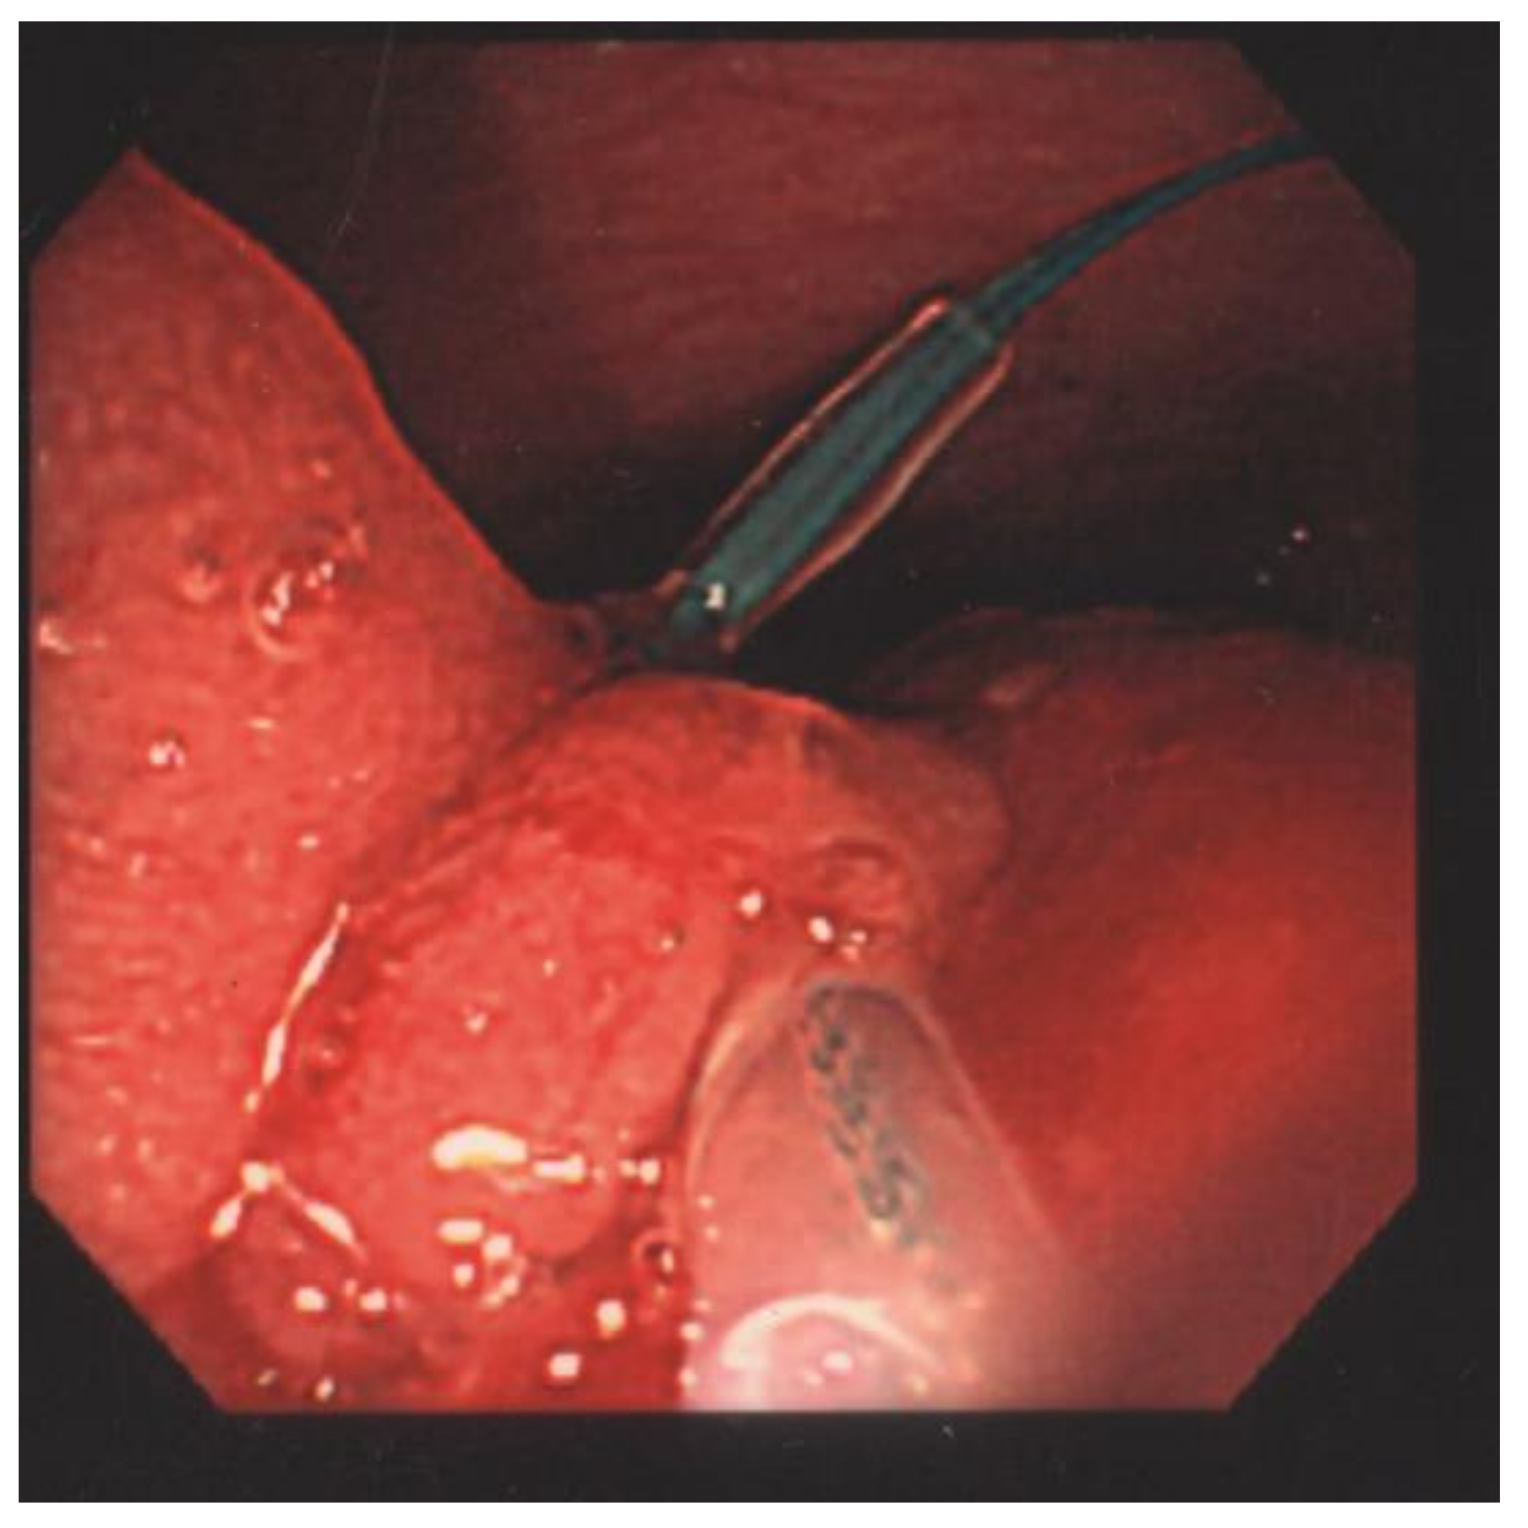

Endoloop-Assisted Polypectomy for a Symptomatic Giant Colonic Polyp in a Pediatric Patient

2. Laboratory Results and Treatment